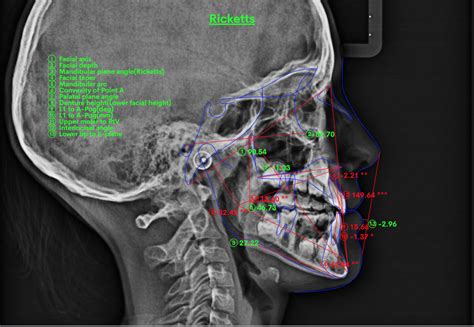

La cefalometría de Ricketts es un análisis exhaustivo que considera múltiples ángulos y medidas para evaluar el crecimiento craneofacial y las relaciones dentales. Este análisis ayuda a los ortodoncistas a comprender la complejidad de cada caso y a diseñar planes de tratamiento personalizados.

La cefalometría es una herramienta fundamental en la ortodoncia, permitiendo analizar las relaciones esqueléticas y dentales del paciente a través de mediciones angulares y lineales en radiografías laterales de cráneo. Estos ángulos proporcionan información valiosa para el diagnóstico y la planificación del tratamiento ortodóncico.

A continuación, se describen algunos ángulos cefalométricos importantes y su interpretación: